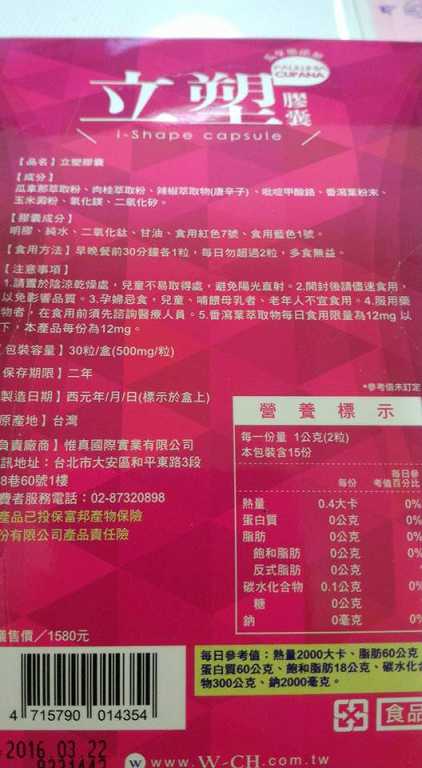

每一盒Supercut塑魔纖立塑膠囊都有三小包,每一小包有10顆膠囊

Supercut塑魔纖立塑膠囊的成分有:瓜拿那萃取粉、肉桂萃取粉、辣椒萃取物(唐辛子)、吡啶甲酸鉻、番瀉葉粉末、玉米澱粉、氧化鎂、二氧化矽。

之前上過相關課程,成分表是依照每項成分的多寡來排列順序,排在最前面的就是產品的主要成分!

食用方式:早晚餐前30分鐘各1粒,每日不超過2粒。(多食無益)

包裝是桃紅色的

番瀉葉萃取物每日食用限量為12mg以下,